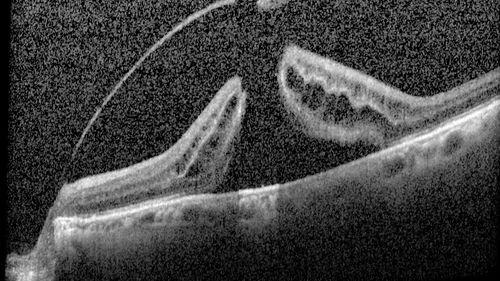

Macular Hole with Limited Retinal Detachment

87 year old female with decreased vision in the left eye for 2 months.  VA 5/200.  Initial three images are pre-op.  Then there is 3 months 6 months and 9 months post-op scans.  VA improved at 1 year to 20/50.  Surgery was done with Brilliant Blue.